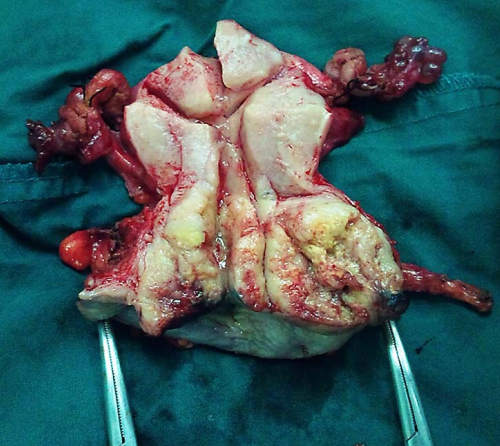

1.手术治疗 手术的优点是年轻患者可保留卵巢及阴道功能。主要用于早期子宫颈癌(ⅠA~ⅡA期)患者。①ⅠA1期:无淋巴脉管间隙浸润者行筋膜外全子宫切除术,有淋巴脉管间隙浸润者按ⅠA2期处理。②ⅠA2期:行改良广泛性子切除术及盆腔淋巴结切除术或考虑前哨淋巴结绘图活检(sentinel lymphnode mapping)。③ⅠB1期、和ⅠB2期ⅡA1期:行广泛性子宫切除术及盆腔淋巴结切除术或考虑前哨淋巴结绘图活检,必要时行腹主动脉旁淋巴取样。④部分ⅠB2期和ⅡA2期:行广泛性子宫切除术及盆腔淋巴结切除术和选择性腹主动脉旁淋巴结取样;或同期放、化疗后行全子宫切除术;也有采用新辅助化疗后行广泛性子宫切除术及盆腔淋巴结切除术和选择性腹主动脉旁淋巴结取样。未绝经、<45岁的鳞癌患者可保留卵巢。要求保留生育功能的年轻患者,ⅠA1期无淋巴脉管间隙浸润者可行子宫颈锥形切除术(至少3cm阴性切缘);ⅠA1期有淋巴脉管间隙浸润和ⅠA2期可行子宫颈锥形切除术加盆腔淋巴结切除术或考虑前哨淋巴结绘图活检,或和ⅠB1期处理相同;一般推荐ⅠB1期行广泛性子宫颈切除术及盆腔淋巴结切除术或考虑前哨淋巴结绘图活检,但若经腹或腹腔镜途径手术,手术指征也可扩展至ⅠB2期。

Ⅲ型即广泛子宫切除术标本 盆腔淋巴结切除术标本